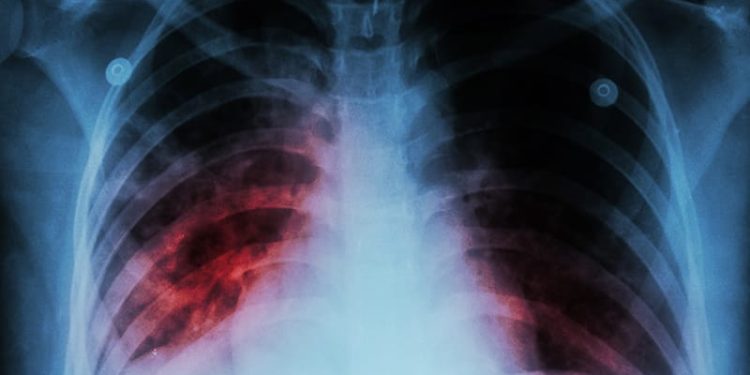

While for the past 30 years, the incidence of active tuberculosis (TB) in the US has been lower than the global incidence, untreated latent TB infection (LTBI) is thought to account for the majority of domestic infections. In fact, about 80% of US active TB cases may have progressed from LTBI that was untreated…